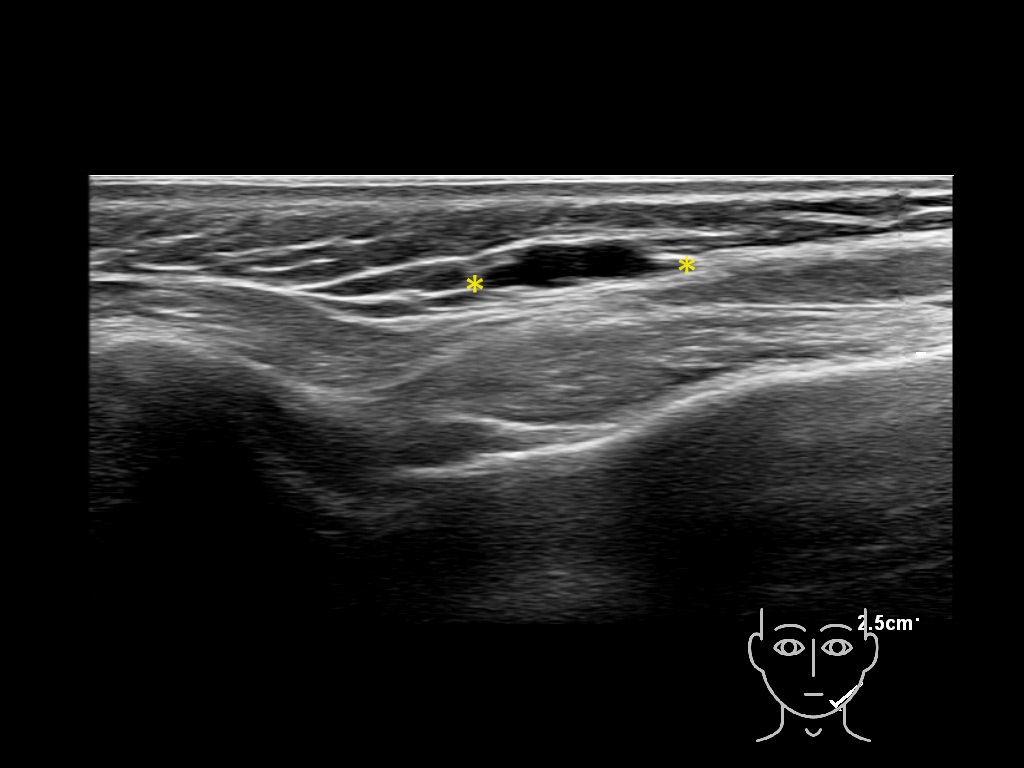

Study the first image to recognize the different layers. If you are sure about the layers, swipe to the second image to view the answer (if applicable).